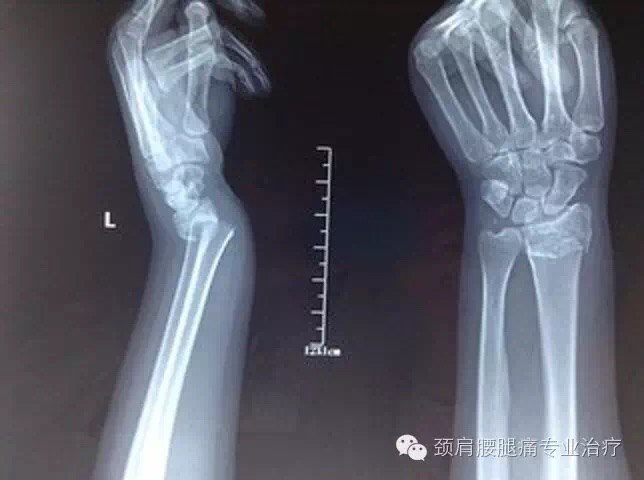

骨科小白第一次柯氏骨折手法复位请求老师们指导一下

图片尺寸4000x3000